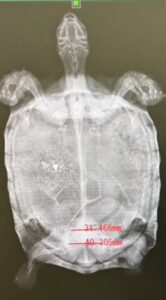

実はこの亀さん、去年時点でのレントゲンで腹腔内に結石がありました。その時はまだ小さかったのと一般状態が良かったので経過観察としていました。しかし、時間経過と共に結石は巨大化していました。結石の直径は骨盤を通るか通らないかまでになっており、自然排泄は難しいと判断して用手にて摘出することにしました。

そのままでは、亀さんも動いてしまいますのでアルファキサンで鎮静してトラマール注で鎮痛処置をして挑みました。完全に不動化し筋弛緩が起きると総排泄腔も弛緩します。しかし、この大きい結石は大変難儀しました。心が折れそうになり開甲術なども頭によぎりましたが無事摘出できました。